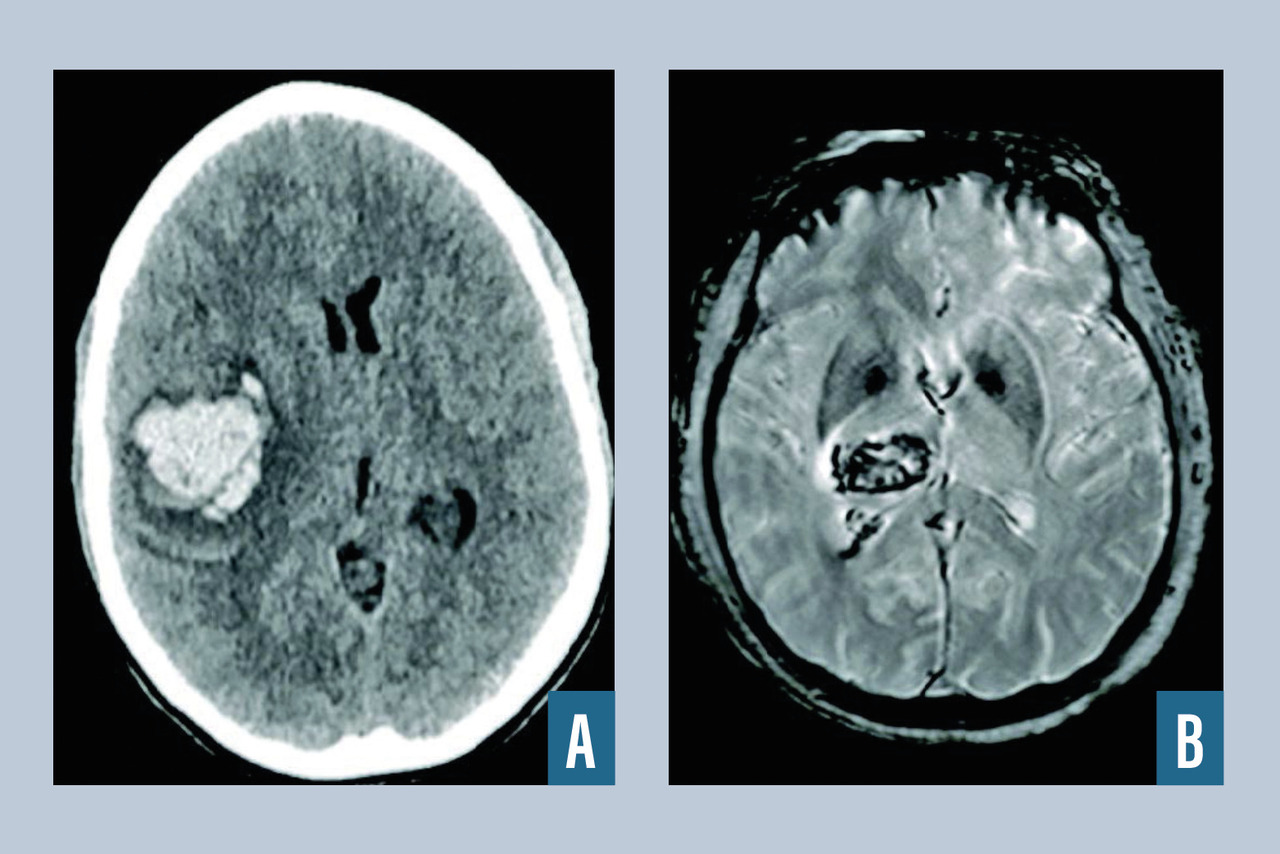

Hématomes intraparenchymateux

L’hématome intracérébral est une collection de sang consécutive à la rupture d’un vaisseau intracrânien (fig. 2 ). L’hypertension artérielle est la première cause, et l’hémorragie est alors très souvent localisée au niveau des noyaux gris centraux. Lorsque l’hémorragie est située en superficie, elle est dite lobaire, et après 50 ans, le diagnostic d’angiopathie amyloïde est fréquemment rencontré après exclusion des autres diagnostics (tumeurs, traumatisme…). Une autre cause est la rupture d’une malformation vasculaire, que ce soit une malformation artérioveineuse, un anévrisme ou un cavernome. Parmi les autres causes, on cite la thrombophlébite cérébrale et les troubles de la coagulation spontanés ou iatrogènes (traitements antithrombotiques). Le scanner cérébral, qui est l’examen de référence en cas d’hémorragie cérébrale, met en évidence une plage en hyperdensité et est le plus souvent complété par un scanner cérébral avec injection et un angioscanner cérébral à visée étiologique (recherche de tumeur, de malformation vasculaire, de thrombose veineuse cérébrale). L’IRM cérébrale avec ARM peut être intéressante lorsque le scanner n’est pas contributif pour rechercher une cause de l’hémorragie (stigmates de maladies des petites artères liées à l'âge et à l'hypertension artérielle, angiopathie amyloïde, tumeur cérébrale). En l’absence de cause retrouvée à la phase aiguë, l’IRM cérébrale injectée doit être réitérée à trois mois pour s’assurer de l’absence de lésion sous-jacente. Le recours à l’artériographie cérébrale est fréquent dans le cadre du bilan étiologique de l’hématome du sujet jeune, en l’absence de cause évidente.